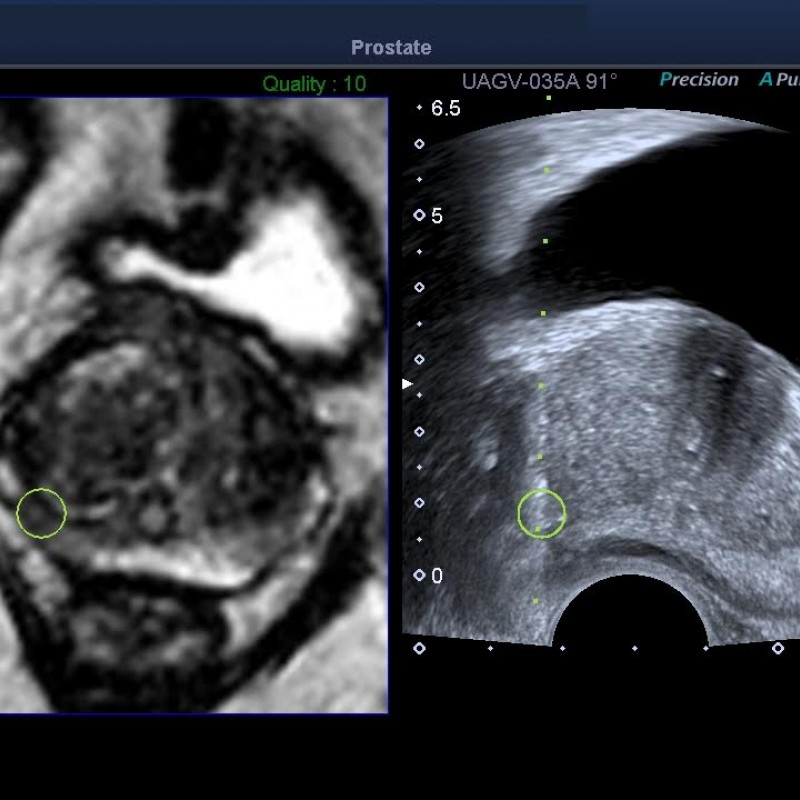

La biopsia guiada por fusión con tecnología Toshiba llega a la medicina privada asturiana.

Es un placer anunciar que Clínica Molinón vuelve a ser noticia a nivel local y nacional por ser centro de medicina privada pionero en innovación médica y tecnológica al emplear la tecnología Smart Fusion de Toshiba en procedimientos de biopsia guiada.

Clínica Molinón, centro pionero Smart Fusion de Toshiba. Leer Más